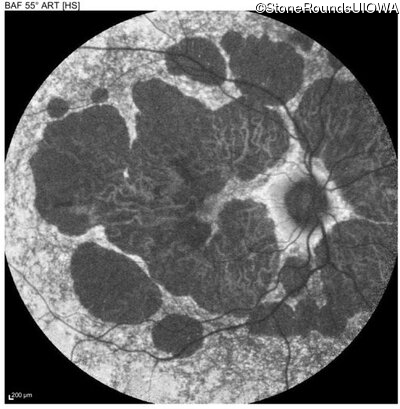

Blue Autofluorescence - Right - 20/40 -2

Exemplar

Blue Autofluorescence - Left - 20/40 +1